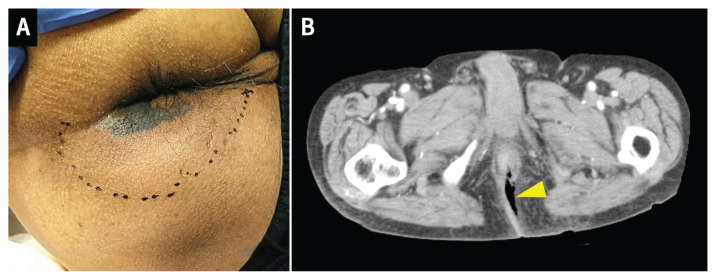

An 84-year-old man was found to be hypotensive before receiving his regularly scheduled dialysis treatment and was referred to our emergency department. He reported slight fatigue but did not have any pain. On arrival, his blood pressure was 58/13 mm Hg and his heart rate was 102 beats/min. He had a normal respiratory rate and was afebrile. He had a score of 15 on the Glasgow Coma Scale (E4, V5, M6). The only potential source of infection that we identified was a small, black skin lesion near the anus, with induration and slight tenderness (Figure 1A). Based on his clinical presentation, we diagnosed perineal fasciitis, also known as Fournier gangrene. We administered intravenous fluids and vasopressor support, and urgently consulted surgery. After stabilization, a computed tomography scan showed subcutaneous free air behind the rectum (Figure 1B).

(A) Black perineal lesion near the anus at initial presentation of an 84-year-old man with Fournier gangrene. An area of induration with slight tenderness is indicated by the dashed line. (B) Computed tomography scan of the perineal lesion, showing free air in the subcutaneous space behind the rectum (yellow arrowhead).